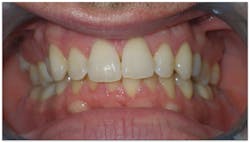

Diagnosis

Everything added up to a diagnosis of maxillary deficiency, which had an adverse effect on the position of the mandible. The patient’s narrow, underdeveloped maxilla also trapped his mandible in a retruded position upon closure.